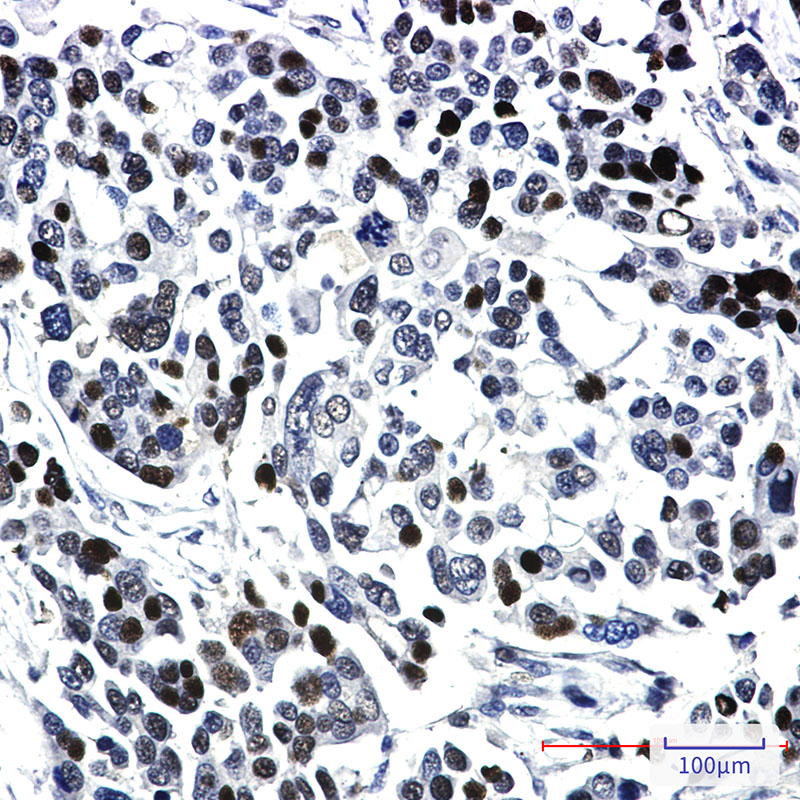

Product Image

| IHC | 1/50-1/100 |